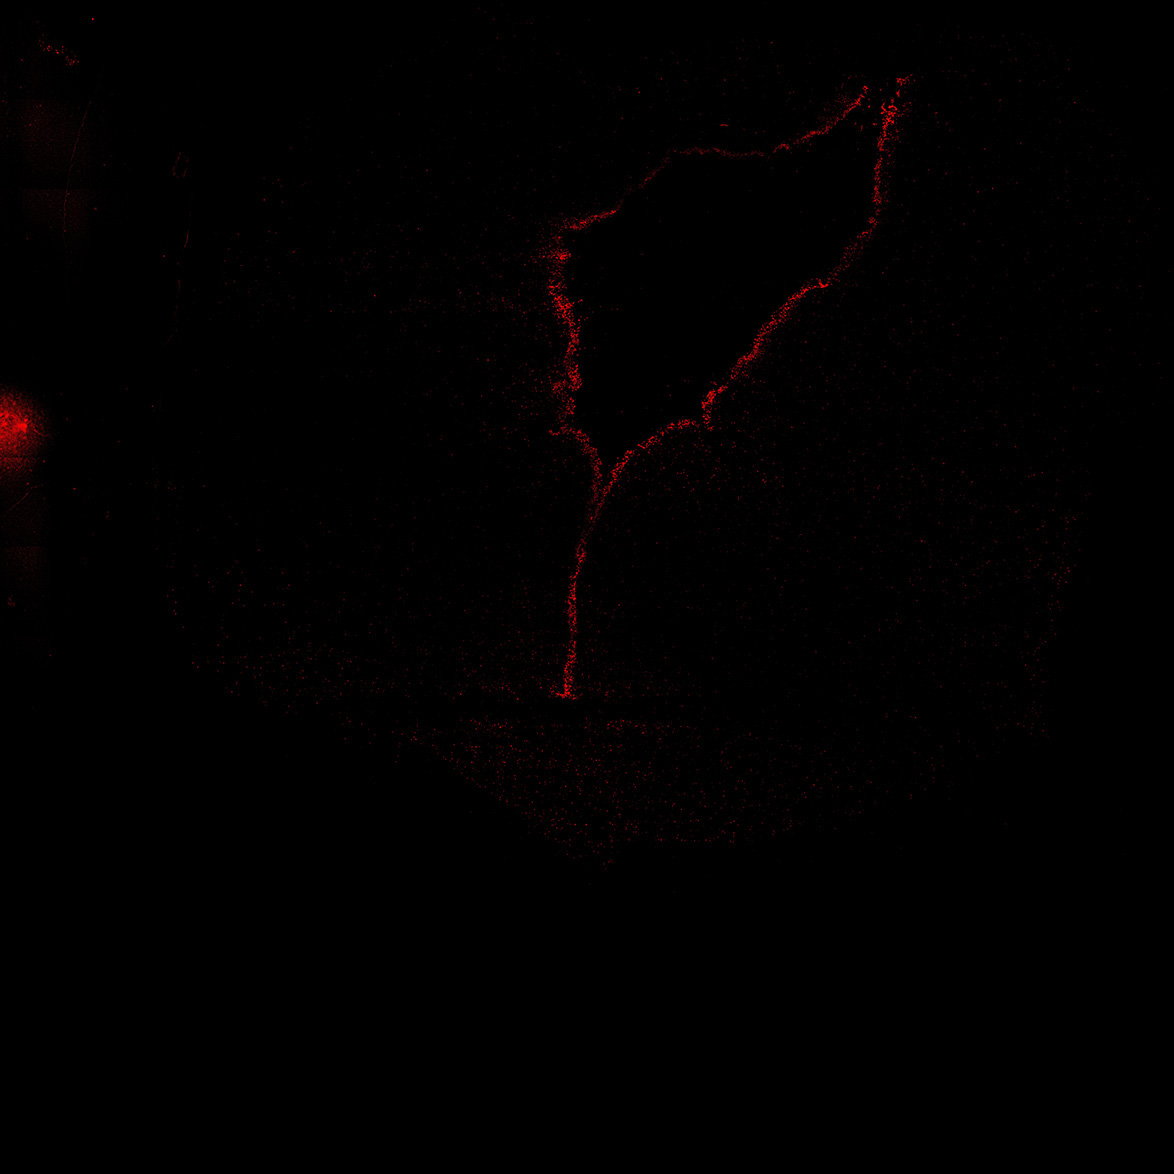

TH

22PCW human midbrain